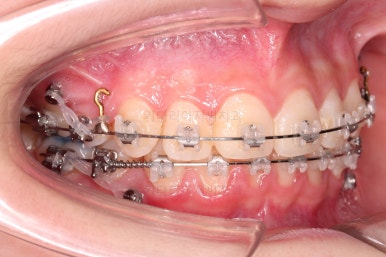

치아 갯수를 맞추고 튀어나온 앞니를 넣기 위해서 윗니 중간의 작은 어금니를 발치를 했고요.

아래는 통째로 앞으로 끌고 나오기로 했습니다.

아래턱은 아쉽게도 성장 시킬 수 있는 나이는 지났고, 대신 가능한 선에서 아랫니를 앞으로 빼보기로 했습니다.

윗니는 틈을 점점 줄여가고요.

아랫니는 중간에 오히려 틈이 생기고 있죠?

이런 효과로 위아래 앞니는 급속도로 가까워지게 됩니다.

아랫니는 이후에 어금니를 앞으로 당겨오면서 빈공간을 줄여 나갑니다.

얼굴모습도 확인해 줍니다.

아랫니와 맞추기 위해서 무리하게 윗니를 뒤로 넣다보면 입매가 망가지거든요.

아랫니도 가능한 앞으로 빼주면서 아랫입술 아래의 푹 들어간 주름을 점점 개선해 줍니다.

교합이 점점 맞아가네요.